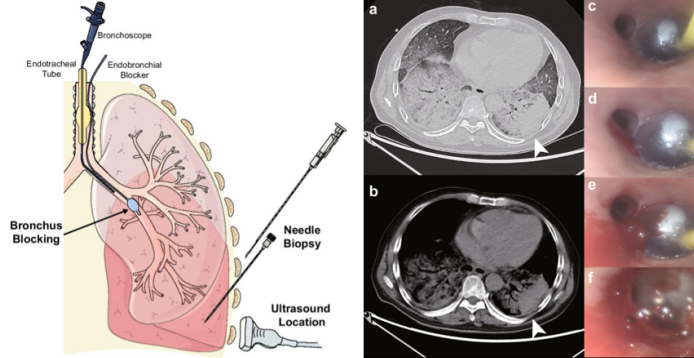

在考虑手术方案时应关注内镜的选择、麻醉方式、人工气道的建立方式及手术方式的选择。①内镜的选择:工作孔径,选用可弯曲支气管镜或者硬质支气管镜。对于高危患者,一般建议采用治疗性支气管镜,如果条件允许,尽量在硬镜下进行操作。②麻醉方式:包括局部麻醉、静脉麻醉、全身麻醉、全身麻醉+高频喷射通气。有麻醉医生在场,可以显著提高操作的安全性。③人工气道的建立方式:可以通过气管插管、喉罩和硬镜事先建立人工气道。一旦在气管镜操作中发生大出血,可以尽快采取气道控制、肺部隔离以及止血等措施。④手术方式:首先应遵循先“微”创、后“巨”创的原则。统计发现,EBUS-TBNA与常规TBNA的大出血的风险很低,其穿刺针直径仅为20 G(不足1 mm),因此创面很小,创伤轻微。对于把握不好的患者,可以先采用TBNA进行活检。其次,可以选择预置球囊的手术方式。对于高出血风险操作(冷冻肺活检、异物摘除、肿瘤冻切)或高出血倾向(病灶部位血供丰富、凝血功能障碍、危重症的高危操作、近期大咯血)的患者,可以预置球囊。2021年,四川大学华西医院呼吸与危重症医学科的同道开创了一种新的实用且可行的方法,即对ICU重症患者经皮肺穿刺活检,他们采用了经支气管放置球囊来保障患者的安全,取得了很好的效果[8]

图片

图源:Crit Care, 2021, 25(1):359.